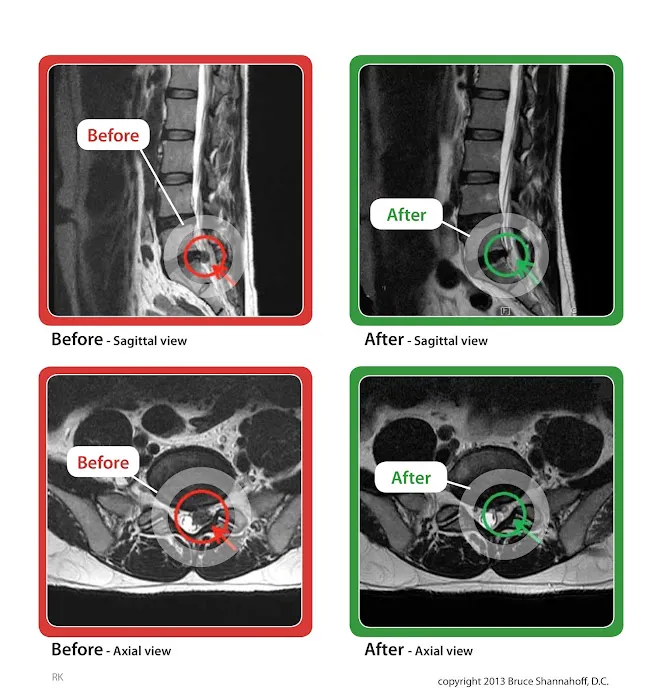

- Spinal Decompression Therapy (DRX9000): Utilizing the state-of-the-art DRX9000 machine, this therapy gently stretches the spine to create negative pressure within the discs. This process helps to reposition herniated or bulging discs, allowing vital nutrients and oxygen to flow back into the disc for healing, and relieving pressure on nerves.

- Proven Track Record with Severe Cases: The testimonials highlight success stories even with significant disc herniations (e.g., 11mm lumbar disc), where other medical professionals suggested surgery. This demonstrates the effectiveness of their therapy even in severe, debilitating situations.

- Rapid and Sustained Pain Relief: Patients often report significant improvement within a few visits or weeks, with dramatic pain reduction (e.g., 90% gone by the 15th visit) and complete elimination of pain within 10 weeks for some. The therapy helps the body heal itself, leading to lasting results.

- Genuine Alternative to Surgery and Injections: The center provides a viable and highly effective alternative for patients who wish to avoid invasive spinal surgery, the risks associated with it, or repeated steroid injections. This offers immense peace of mind and preserves quality of life.